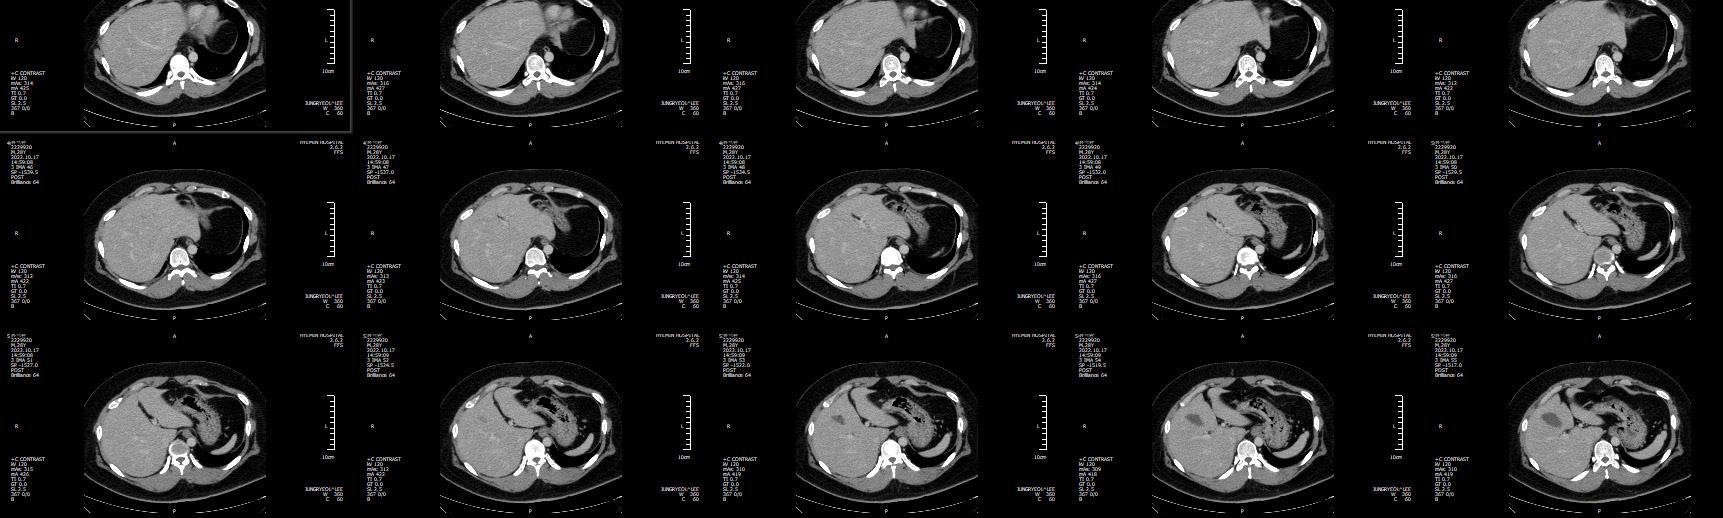

RT-PCR ๊ฒ€์‚ฌ ๋Œ€์ƒ์ž ๋ฐ ๋ฐฉ๋ฒ•

์‘๊ธ‰์‹ค์— ๋‚ด์›ํ•˜์—ฌ ์ž…์›์ด ํ•„์š”ํ•œ ๋ชจ๋“  ํ™˜์ž๋Š” ๋ณ‘์‹ค ์ž…์‹ค ์ „ ์ฝ”๋กœ๋‚˜19 RT-PCR ๊ฒ€์‚ฌ๋ฅผ ์‹œํ–‰ํ•˜๊ณ  ๊ฒ€์‚ฌ๊ฒฐ๊ณผ ํ™•์ธ ์ „๊นŒ์ง€ ๊ฒฉ๋ฆฌ ๋ณ‘์ƒ์—

์„œ ๋Œ€๊ธฐ ํ›„ ๊ฒ€์‚ฌ ๊ฒฐ๊ณผ ์Œ์„ฑ์œผ๋กœ ํ™•์ธ ์‹œ ์ผ๋ฐ˜๋ณ‘์‹ค๋กœ ์ด๋™ํ•˜๋„๋ก ํ•˜์˜€๋‹ค. ์‘๊ธ‰์‹ค์— ๋‚ด์›ํ•˜์—ฌ ์ž…์›์„ ํ•˜์ง€ ์•Š๋”๋ผ๋„ ๊ณ ์—ด ๋˜๋Š” ํ˜ธํก๊ธฐ ์ฆ

์ƒ์ด ์žˆ๊ฑฐ๋‚˜ X-ray ๋˜๋Š” CT ์ดฌ์˜์—์„œ ํ๋ ด์ด ์˜์‹ฌ๋  ์‹œ์—์„œ ์ฝ”๋กœ๋‚˜19 RT- PCR ๊ฒ€์‚ฌ๋ฅผ ์‹œํ–‰ํ•˜์˜€๋‹ค. ์ฝ”๋กœ๋‚˜19 RT-PCR ๊ฒ€์‚ฌ๋Š” ๋ณ‘

์› ๋ฐ– ์ฝ”๋กœ๋‚˜ ๊ฒ€์‚ฌ ๋ถ€์Šค์—์„œ ์‹œํ–‰ํ•˜์˜€๊ณ  ์ด๋™์ด ํž˜๋“  ์ค‘ํ™˜์ž์˜ ๊ฒฝ์šฐ ์‘๊ธ‰์‹ค ์Œ์••๊ฒฉ๋ฆฌ์‹ค ๋‚ด ์นจ์ƒ์—์„œ ์˜๋ฃŒ์ง„ ๋ณดํ˜ธ๋ณต ์ฐฉ์šฉ ํ›„ ์‹œํ–‰ํ•˜๊ธฐ ๋„ ํ•˜์˜€๋‹ค.